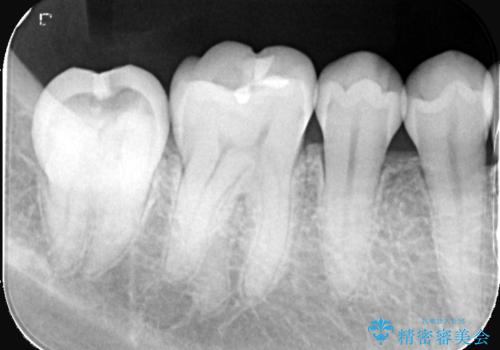

- 頬側に大きな虫歯があり、神経に達している可能性が高かったため、虫歯除去時に神経が出た場合はVPTを提案しました。

虫歯が神経まで達していましたが、術前の検査でVPTの適応と診断をしていたので、ラバーダムシートを装着しVPTを行いました。

経過も良好で、痛みも無く神経を残すことが出来ました。